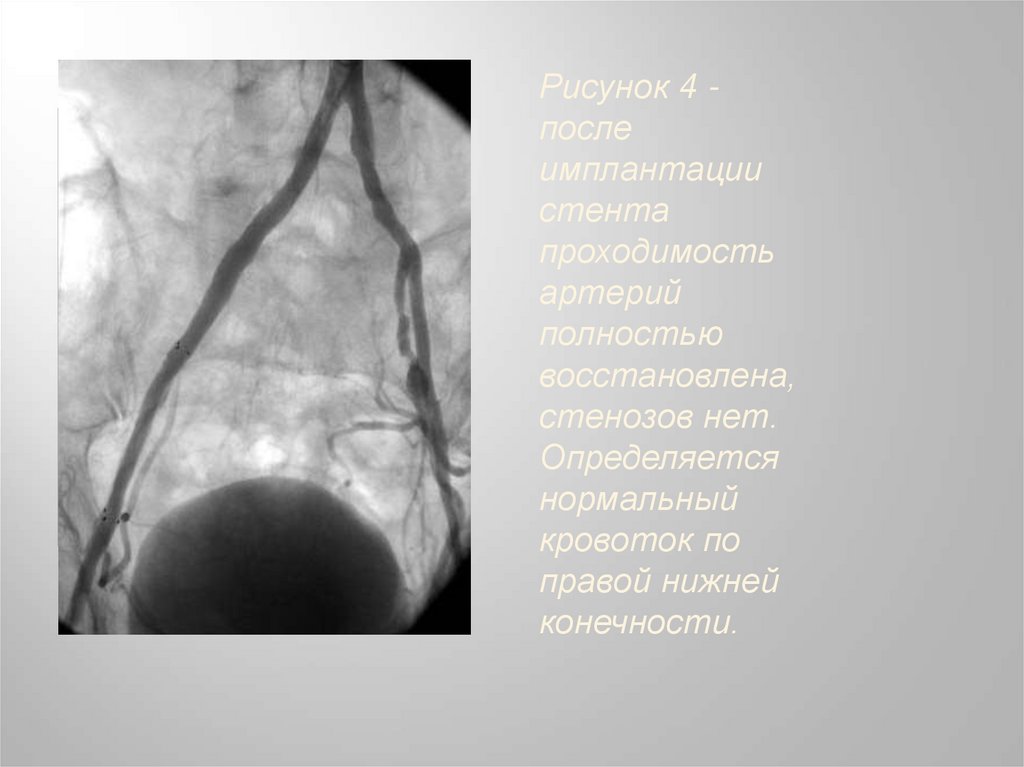

При контрольной артериографии

отмечается полное восстановление

просвета сосуда и кровотока в нем (Рис.4).

Рисунок 4 после

имплантации

стента

проходимость

артерий

полностью

восстановлена,

стенозов нет.

Определяется

нормальный

кровоток по

правой нижней

конечности.